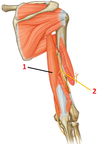

1?

1: Deltoid muscle

1?

Pectoralis major muscle